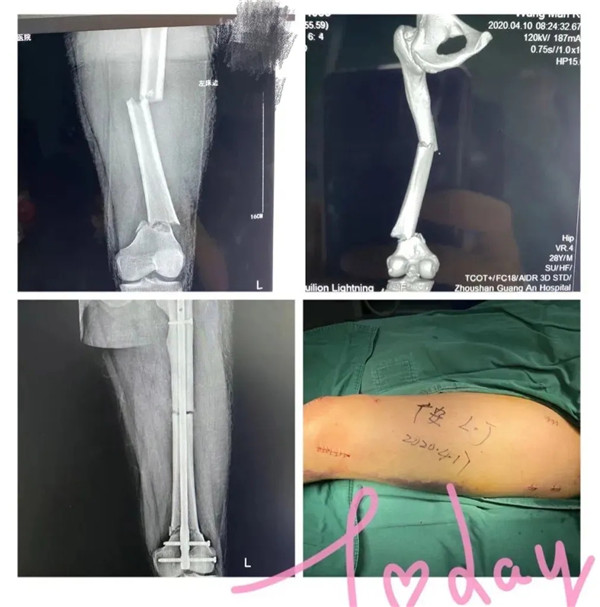

受傷的是家住城北的年輕小伙小王,早上騎電動車去上班速度太快而不慎摔傷。急診醫(yī)生初步檢查,判斷是大腿骨骨折,立即予以拍片檢查。結(jié)果顯示:左股骨多段粉碎性骨折。小王左腿股骨竟斷成三截 !須做手術(shù)治療。病人和家屬看到片子后,都有點(diǎn)嚇傻了,急得語無倫次,不斷地追問醫(yī)生:“醫(yī)生,這該怎么辦呢?骨頭都斷這樣了,還能接好嗎?……”醫(yī)生趕緊安撫病人和家屬:“到了我們醫(yī)院,您們放心好了。等檢查完善后,我們會盡快施行手術(shù)治療的”。小王當(dāng)即辦理了住院手續(xù)。

4月17日,在經(jīng)過周密的術(shù)前準(zhǔn)備,小王的身體狀況符合手術(shù)指征,并征得家屬同意后,廣安骨科中心副主任羅軍帶領(lǐng)團(tuán)隊為他實(shí)施了閉合復(fù)位磁力導(dǎo)航髓內(nèi)釘內(nèi)固定微創(chuàng)手術(shù)。

手術(shù)在腰部麻醉下進(jìn)行,術(shù)中僅需幾個微創(chuàng)小切口,創(chuàng)傷小,出血少,一個小時后,手術(shù)順利完成。術(shù)后患者病情很快恢復(fù),生命體征平穩(wěn)。第二天,小王就可以拄拐下地活動并進(jìn)行康復(fù)鍛煉。日前,在醫(yī)護(hù)團(tuán)隊的精心照料下,他已出院回家休養(yǎng)。出院前,小王對著醫(yī)護(hù)人員豎起了大拇指:“廣安醫(yī)院的醫(yī)生技術(shù)好、態(tài)度佳,真牛!”

據(jù)介紹,此次為小王實(shí)施的磁力導(dǎo)航髓內(nèi)釘內(nèi)固定手術(shù)以交鎖髓內(nèi)釘技術(shù)為基礎(chǔ),以新興的磁力導(dǎo)航技術(shù)為依托,以微創(chuàng)為特點(diǎn)。相比傳統(tǒng)手術(shù),定位更加準(zhǔn)確,具有減少手術(shù)時間、減少手術(shù)出血和創(chuàng)傷、減少術(shù)中放射次數(shù),且術(shù)后恢復(fù)快,傷口小,基本不留明顯疤痕的優(yōu)點(diǎn),在磁力導(dǎo)航下,實(shí)現(xiàn)骨折部位的精準(zhǔn)復(fù)位。患者術(shù)后僅一天就可以開始扶拐下地活動并進(jìn)行康復(fù)鍛煉。